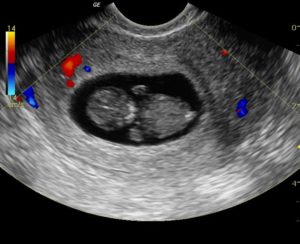

Показатели УЗИ

• Сердцебиение эмбриона не определяется. В норме на ультразвуковом исследовании оно заметно, начиная с 5 недели беременности.

• Плодное яйцо не имеет диаметра таких размеров, которые предполагает срок беременности.

• Величина эмбриона, находящегося в плодном яйце, не соответствует сроку беременности.

• Если срок до 4 недель, то признаком гибели плодного яйца является деформация.

• Эмбрион не визуализируется на сроке 6 – 7 недель.